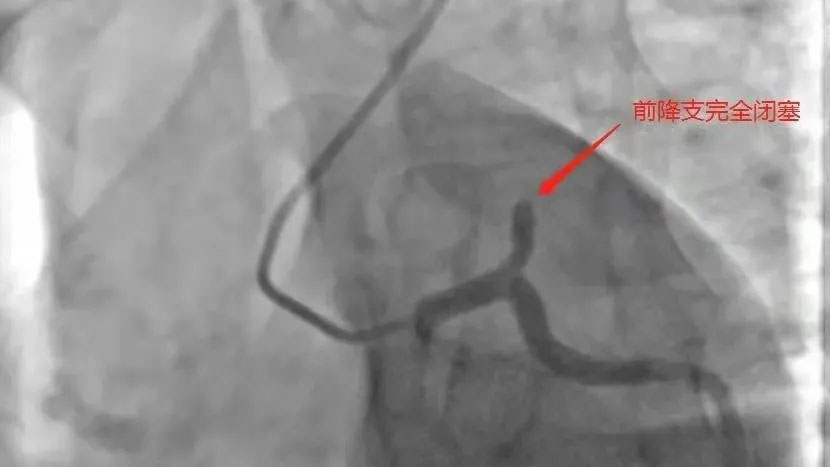

据了解,该患者为34岁男性患者,1年前在上级医院已做过支架植入术,近期反复熬夜及劳累,前段时间已经开始有胸痛症状,因为上过支架没有引起重视,12月31日早上10时许胸痛加重,14:20分进入我院急诊科,急诊科值班医师通过简单询问,14:27分完善首份心电图,考虑广泛前壁心肌梗塞可能,立即上传心电图于来凤县胸痛中心群,心内科值班医师立即建议阿司匹林肠溶片300mg.氯吡格雷600mg,瑞舒伐他汀钙20mg,此时该院常规冠状动脉造影术刚结束,导管室护士正在清理东西准备关闭导管室,心内科朱主任看见上述情况后立即通知导管室做好准备,亲自到急诊科评估患者情况,并电话立即联系副院长兼心内科主任张承中以及刚做完手术回家的恩施慧宜医疗集团张宏伟教授,张宏伟教授了解情况后建议立即开展急诊冠状动脉造影,绕行CCU,直接由急诊科送入导管室,14:50分进入导管室,造影可以看见前降支近端闭塞,原支架内大量血栓堵塞,15:30经球囊扩张后,患者血流有所恢复,因前降支原支架内大量血栓,术中又使用腔内溶栓术、预扩球囊刺破腔内给药、血栓抽吸术等,患者前降支闭塞血管血流恢复,仅用70分钟,为患者开通血管,挽救了患者年轻生命。